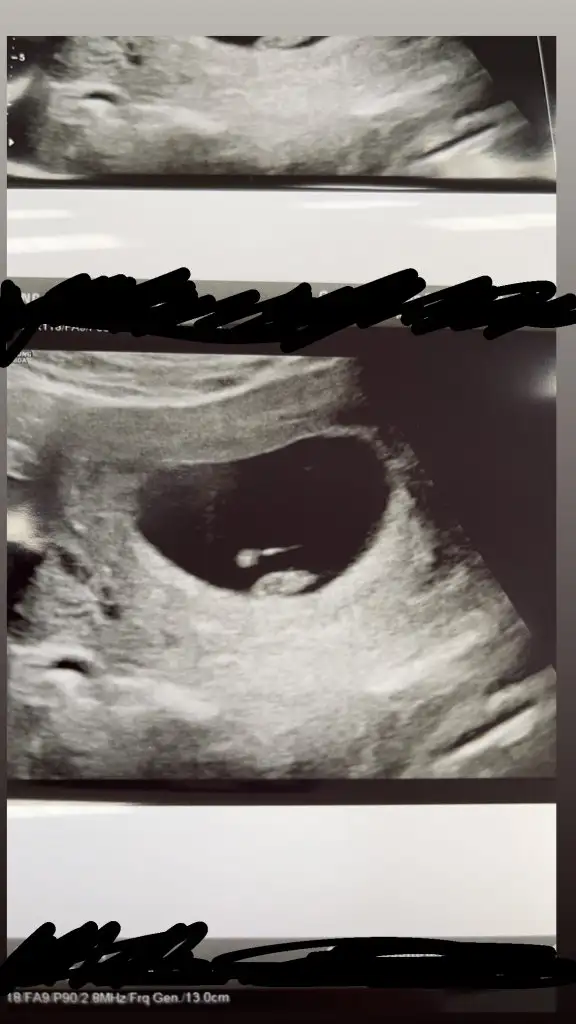

Bana da yorum yapabilir mısınız acaba 7+1 vajinal

Eklentiler

• 16431973968671822837059084314472.webp

16431973968671822837059084314472.webp

11,6 KB · Görüntüleme: 91